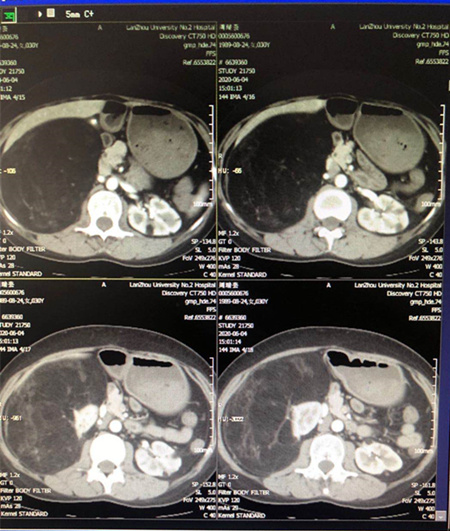

患者,女性,30岁。入院前一年曾已辗转北京、上海、西安等多家医院,经多地专家会诊,确诊为结节性硬化症,目前口服依维莫司10月余,经腹部CT提示右肾巨大占位,直径约30cm,与下腔静脉关系密切。入院后,泌尿外科立即开展病情讨论,评估患者手术指征,并建议手术进行手术治疗。当得知可手术治疗后,患者夫妻二人激动的同时又面露难色,表示已就诊多家医院,深知手术风险,尤其是可能面临右肾切除,同时医药费用昂贵,目前已无力承担,想争取做保肾手术。

肿瘤体积巨大,完整切除尚且困难,患者又有保肾意愿,手术难度及风险度较高,这无疑是对外科医生的巨大挑战。根据患者自身情况,泌尿外科从多方面考虑,为患者制定了详细周密的手术计划。6月11日,杨立、董治龙主任团队为患者实施右肾巨大肿物切除术,手术过程顺利,最终成功保留肾脏,术后病检提示为血管平滑肌脂肪瘤。